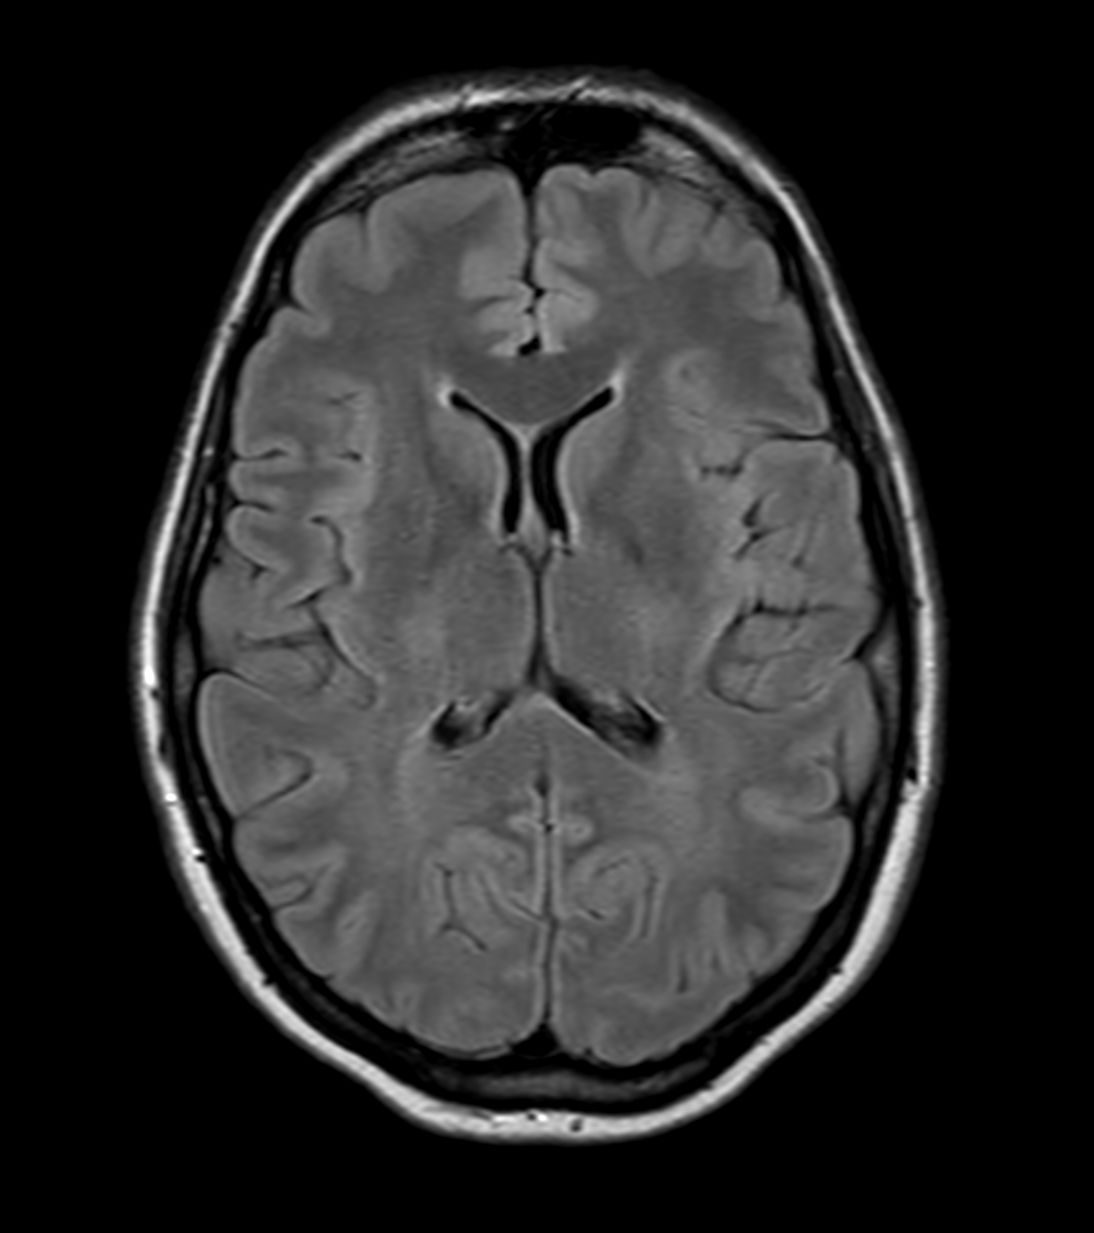

Alzheimer’s Disease Anti-Amyloid Immunotherapies (ARIA) 3.0T

Amyloid clearing medication, such as Aduhelm (Aducanumab) and Leqembi (Lecanemab) have been cleared by the FDA in 2022/2023, to slow down cognitive decline in early-stage Alzheimer’s disease. ASNR-recommendations for AD therapeutic imaging were published in 2022 for eligibility assessment as well as for monitoring for amyloid-related imaging abnormalities. This ExamCard includes ASNR-recommended consensus protocols for imaging of Alzheimer’s Disease Anti-Amyloid Immunotherapies (ARIA). (Cogswell et al., AJNR 2022,43(9)E19-E35;DOI: https://doi.org/10.3174/ajnr.A7586))